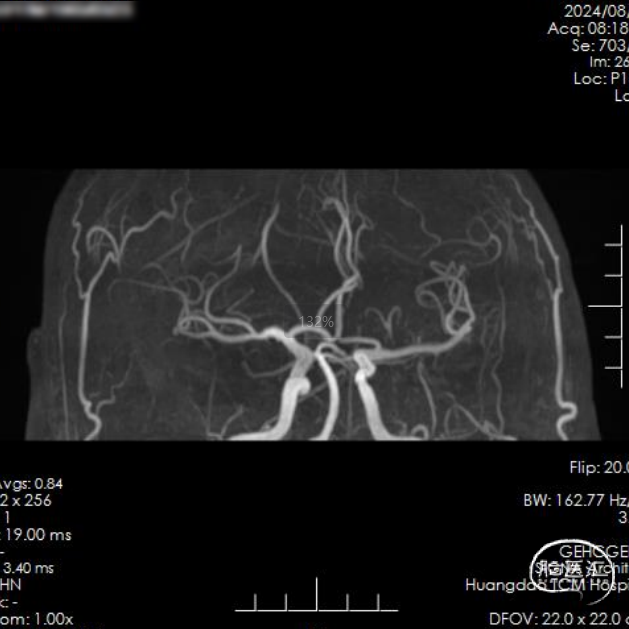

术前影像学检查

CT平扫:未见急性脑梗死早期病灶显影,未见大脑中动脉高密度征。

造影示:左侧颈总动脉显示左侧颈内动脉、大脑前动脉及其分支显影好,左侧大脑中动脉上干前向血流缓慢,提示闭塞。

后续完善磁共振检查:DWI示左侧皮层少许点状高信号,MRA示大脑中动脉分支显影良好。